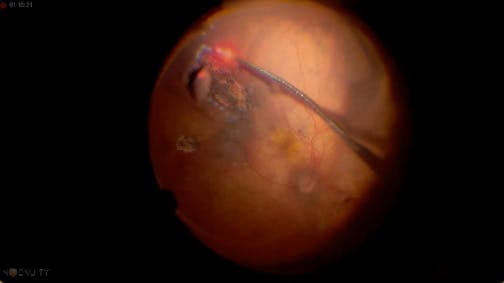

Myopic Macular Hole

Jose Garcia Arumi, MD